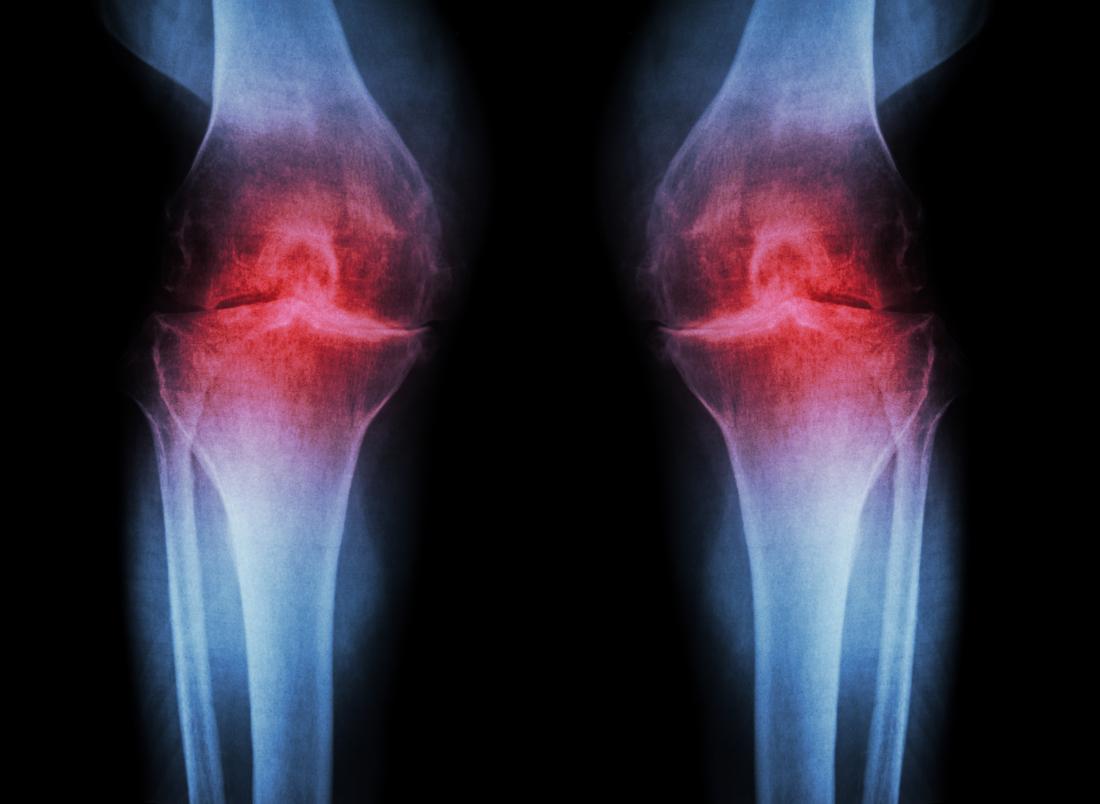

Μπορεί οι χόνδροι, το υλικό που προστατεύει από την τριβή και τελικά τη φθορά τις αρθρώσεις, να μην ανανεώνονται όσο γρήγορα ανανεώνεται το δέρμα, όμως τελικά έχουν και αυτοί την ιδιότητα να αυτοεπισκευάζονται. Η ανακάλυψη του ακριβούς μηχανισμού με τον οποίο συμβαίνει αυτό, δίνει τώρα ελπίδα για τη δημιουργία νέας θεραπείας για την αρθρίτιδα, μία νόσο που ταλαιπωρεί εκατομμύρια ανθρώπους στον κόσμο.

Στο άρθρο τους οι επιστήμονες εξηγούν ότι όσο μία πρωτεΐνη «γερνάει», τόσο και τα δομικά της στοιχεία που είναι τα αμινοξέα (οι πρωτεΐνες αποτελούνται από αμινοξέα) υπόκεινται σε χημικές μεταβολές. Οι ειδικοί μελέτησαν τον ρυθμό που μεταβάλλονται αυτά τα μόρια που σχηματίζουν τον χόνδρο και ανακάλυψαν ότι πιο γρήγορα στη ζωή μας αλλάζει η σύσταση του χόνδρου στο γόνατο και το ισχίο, παρά στους αστραγάλους. Για αυτό και ο αστράγαλος μπορεί να αυτοϊαθεί πιο εύκολα.